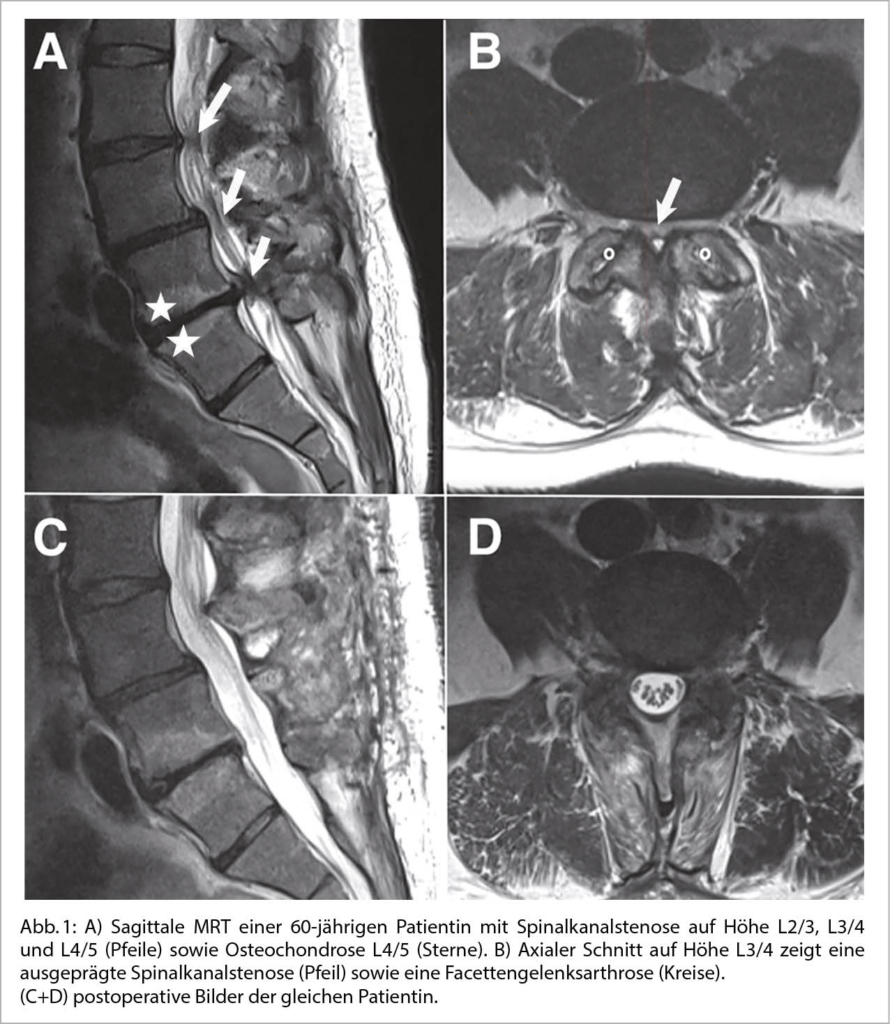

Für die Diagnose einer Spinalkanalstenose sollte schlussendlich jedoch eine MRT erfolgen. Damit können die nervalen Strukturen in Relation zu den umgebenden anatomischen Strukturen wie die Bandscheibe, Facettengelenke und Ligamentum flavum dargestellt werden (Abb. 1).

Differentialdiagnosen wie Diskushernien, Facettengelenkszysten und epidurale Lipomatosen können damit gut differenziert werden.